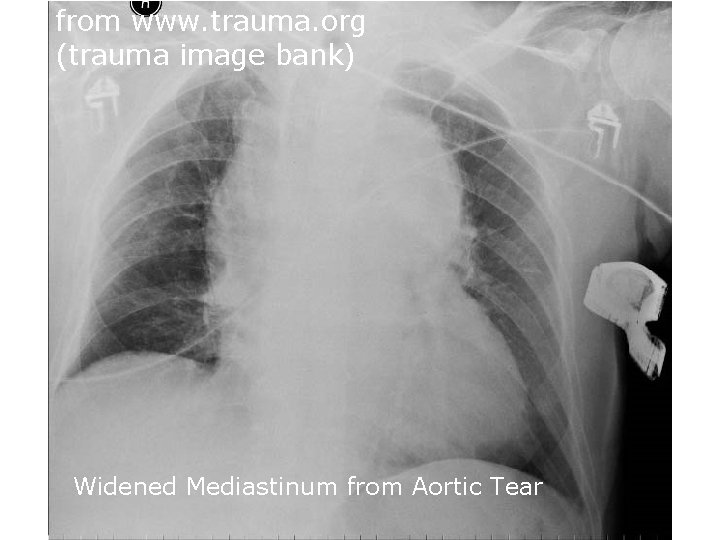

from www. trauma. org (trauma image bank) Widened Mediastinum from Aortic Tear